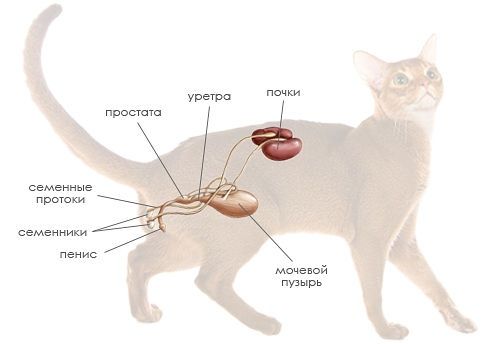

Истончение костей у кошек: причины и решения